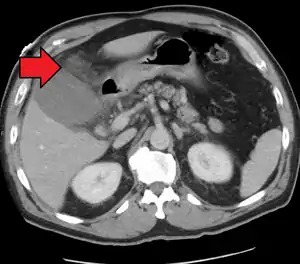

Right upper quadrant abdominal ultrasound is most commonly used to diagnose cholecystitis.[1][26][27] Ultrasound findings suggestive of acute cholecystitis include gallstones, pericholecystic fluid (fluid surrounding the gallbladder), gallbladder wall thickening (wall thickness over 3 mm),[28] dilation of the bile duct, and sonographic Murphy's sign.[13] Given its higher sensitivity, hepatic iminodiacetic acid (HIDA) scan can be used if ultrasound is not diagnostic.[13][14] CT scan may also be used if complications such as perforation or gangrene are suspected.[14]

Acute cholecystitis with gallbladder wall thickening, a large gallstone, and a large gallbladder- Significant gallbladder wall thickening[29]

- Significant gallbladder wall thickening[29]